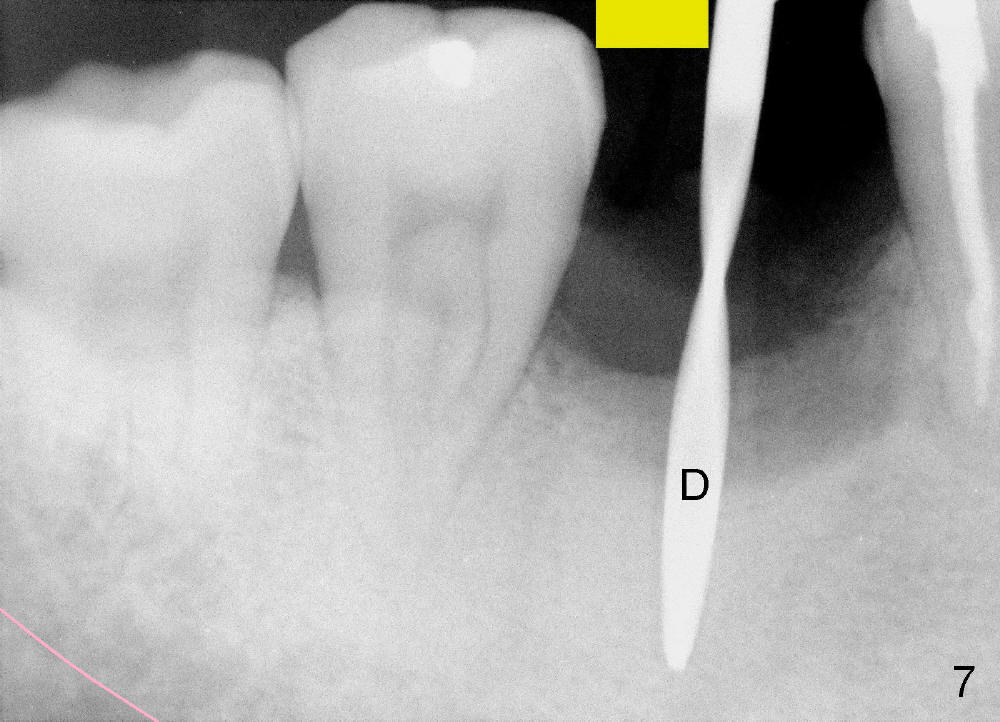

When the pilot drill is inserted into the initial osteotomy site for X-ray confirmation of its depth (Fig.7: D), the vertical block of the endo device (yellow rectangle) may be blocked due to the narrow divided edentulous space. The crown of the molar is shown, whereas the inferior alveolar nerve is not shown except a small portion in the left lower corner of Fig.7 (pink line). The depth of the further osteotomy (Fig.8: O) was chosen without accurate estimate. The integrity of the inferior alveolar canal (IAC) was violated, although the implant (I) was not placed that deep. The patient experienced transient postop pain, which was controlled by Medrol Dosepak. A correct way to prevent iatrogenic neuropathy in this situation is to remove the pilot drill, and place the endo device as deep as possible. The new X-ray should be able to reveal the relationship of the end of the osteotomy (shadow) to IAC. Measurement must be done using digital X-ray software over the new image to determine how deep osteotomy should be made (as shown in Fig.10). When an implant is placed (I in Fig.9: a second case as will be shown in Fig.10-12), the vertical block of the endo device can be placed on the implant. The sensor is placed deep into the lingual vestibule to show IAC in relation to the implant (Fig.8).